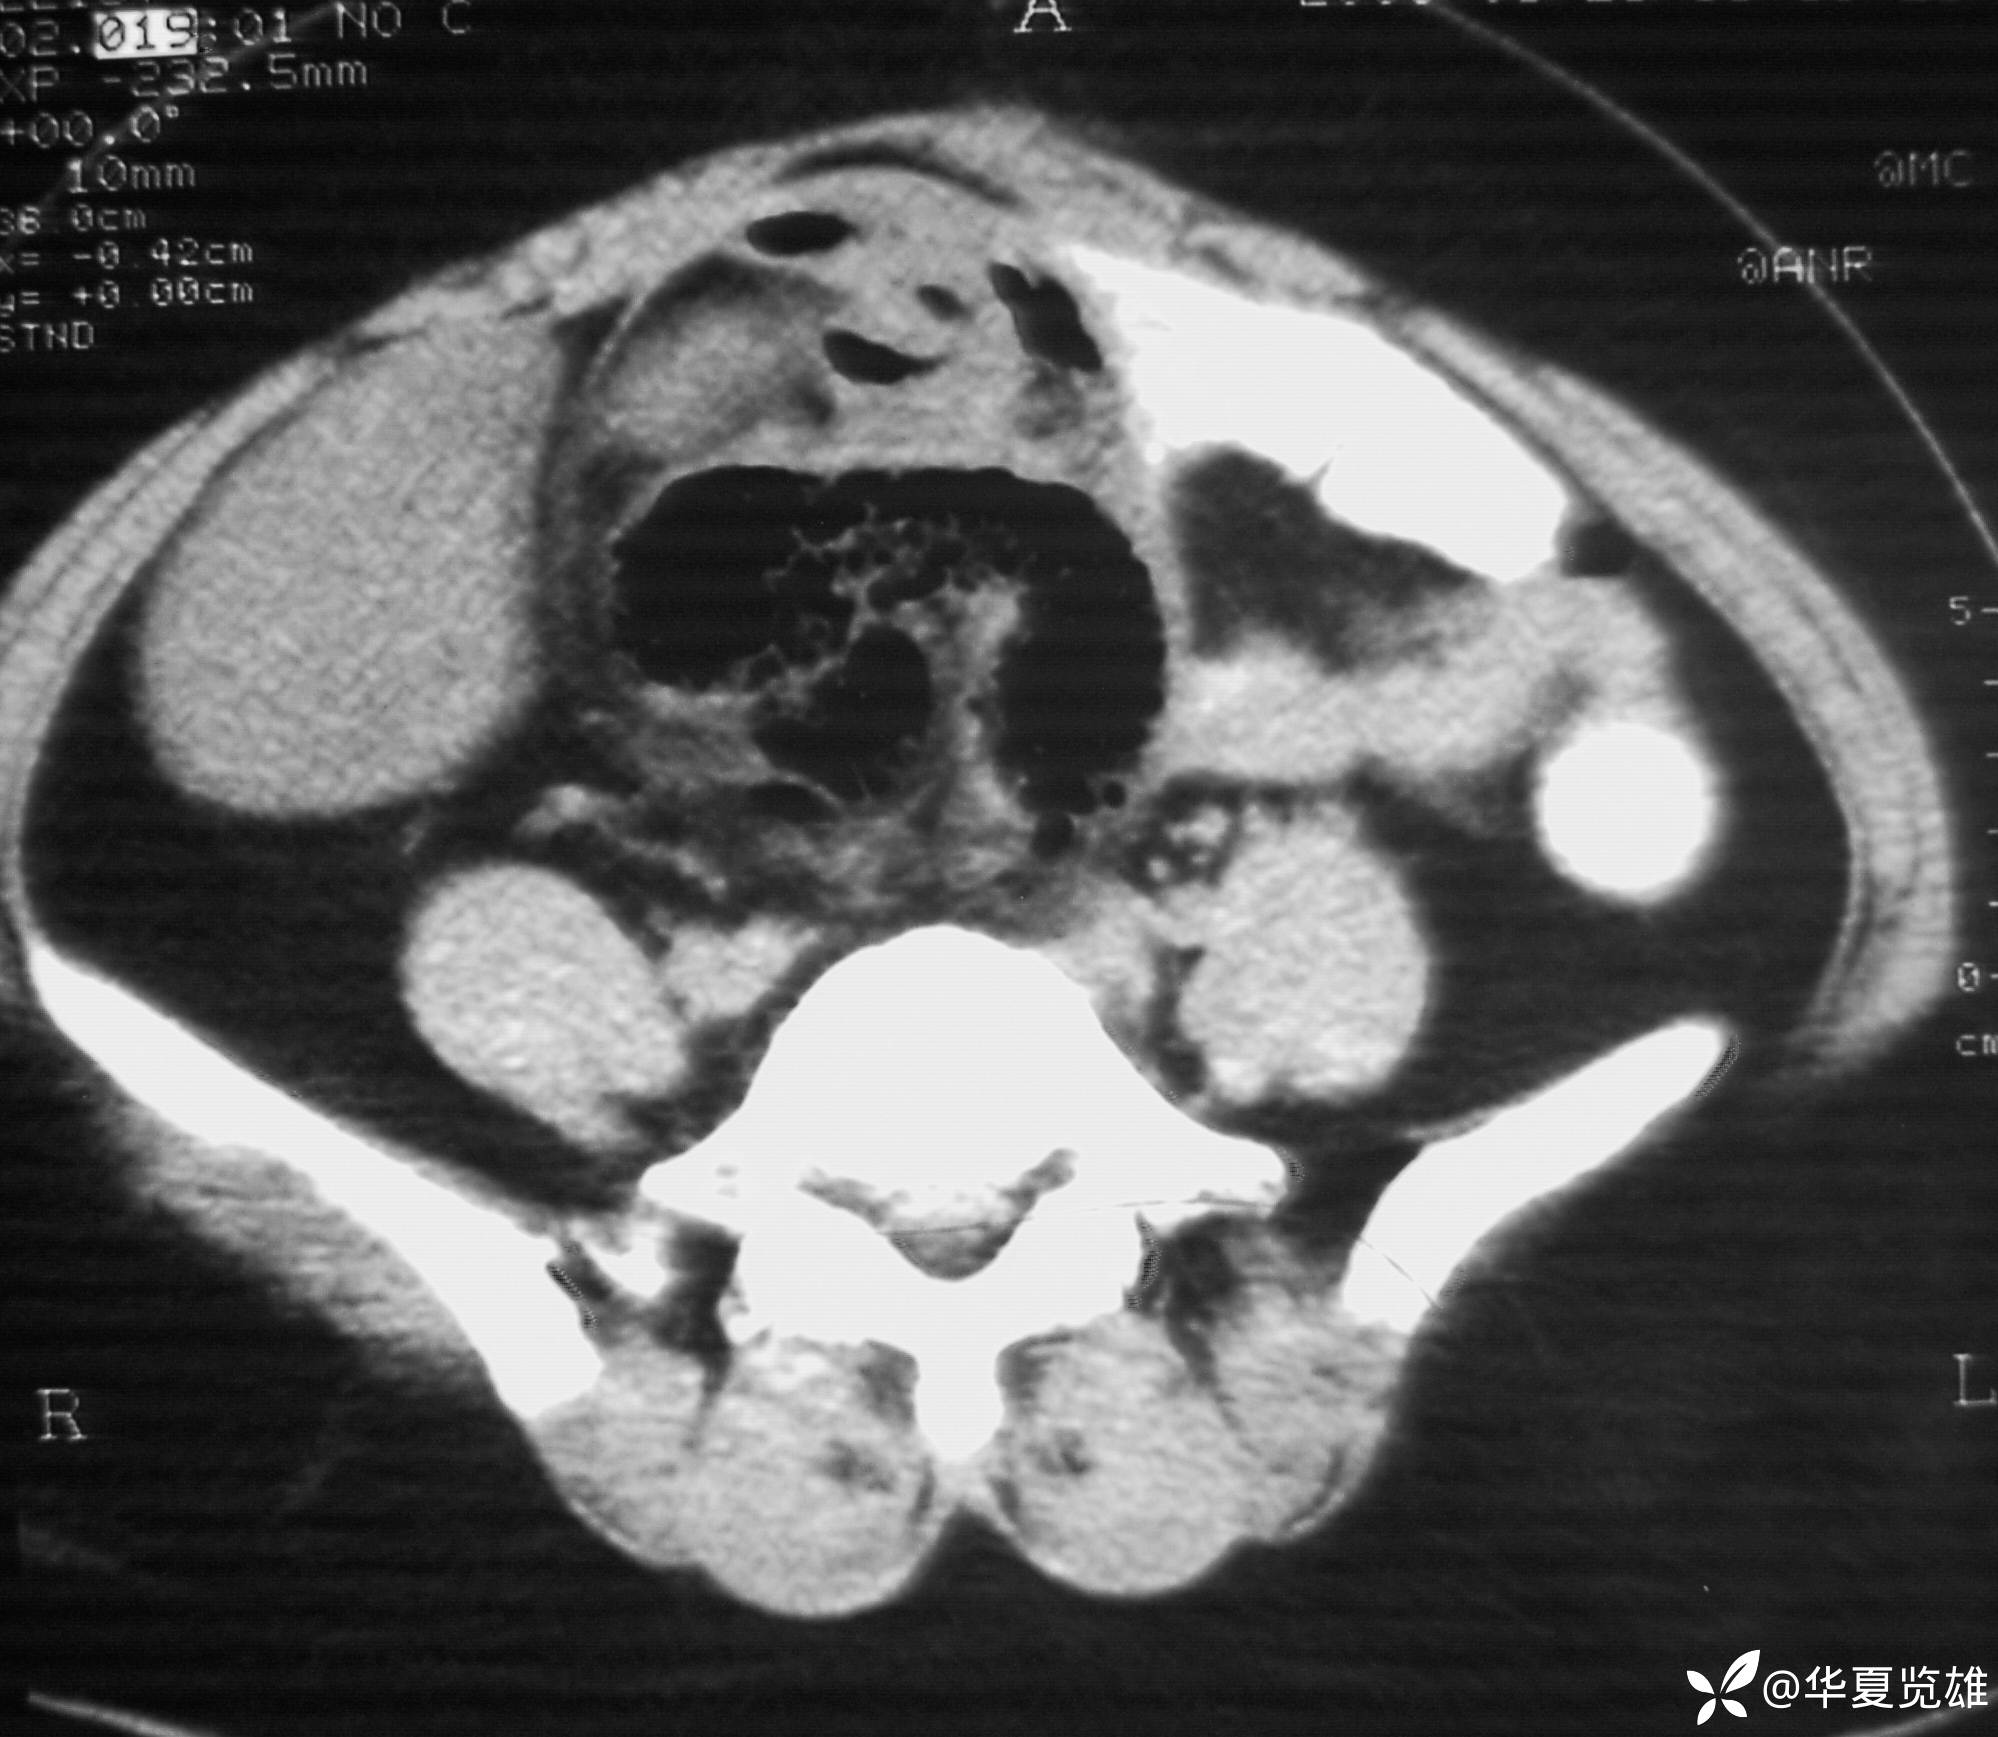

体格检查:下腹部有一纵形手术瘢痕。腹部压痛,无反跳痛。中下腹部扪及一12 cm× 18 cm包块,质韧,压痛。肠鸣音亢进,未闻及气过水音。

红箭-入口;绿箭-出口